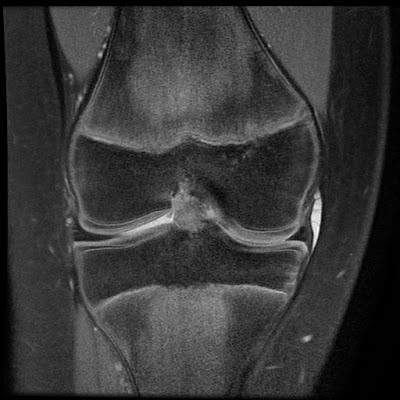

대부분의 정상적인 점액낭은 소량의 점액을 함유하여 MRI에서 잘 관찰되지 않지만, 염증성 변화에 의해 점액양이 증가되면 T1 영상에서 저신호 강도를, T2 영상에서 고신호 강도를 보이는 경계가 명확한 점액낭이 관찰된다.

△ 슬개전 점액낭염(Prepatellar bursitis)의 MRI 소견